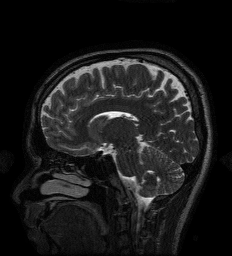

5.6 MRI Experiments

| Original/Mask | PNN | NN | MoDL | GDN2 | GDN1 | TNRD | TV |

| PSNR (dB) | 34.95 dB | 33.09 dB | 34.09 dB | 33.18 dB | 31.37 dB | 32.39 dB | 32.29 dB |

| Test Time (sec) | 16.3 sec | 5.5 sec | 14.3 sec | 5.7 sec | 3.1 sec | 4.0 sec | 349.2 sec |

In this section we provide results of multi-coil MRI reconstruction from undersampled measurements. Full training and test data is the data used for the experiments in [47], consisting of 12-coil Cartesian sampled k-space data of dimension with known coil sensitivity maps. The size of the training set is 360 such acquisitions across 4 subjects, with testing being performed on 40 images from one, separate subject who was not used for training. The sum-of-squares reconstruction is treated as ground truth. Further details of the data acquisition can be found in [47].

All experiments are for 4 undersampling, although we differ from [47] in that we train on a fixed k-space undersampling mask. The undersampling mask is fully sampled in the center 0.15 fraction of frequencies, with the remaining frequencies being sampled according to a random Gaussian pattern. The mask is visualized in figure 10.

For the MRI experiments we follow the precedent set by [47] in our choice of learned component, using only a simple five-layer convolutional network with 64 filters per layer and ReLU nonlinearities for all architectures other than TNRD. The TNRD architecture follows the architecture proposed in [33]. The Neumann network results presented here are for the preconditioned Neumann network (PNN), and the number of blocks for GDN, PNN, MoDL, and TNRD is fixed to be 5. The preconditioning operator in PNN is implemented through 10 conjugate gradient iterations, identically to [47]. We compare to GDN with the same initialization as NN (GDN1) and as PNN (GDN2) to study the effect of different initializations on GDN.

We observe that unrolled optimization approaches are advantageous in this setting compared to the more traditional TV-regularized reconstruction. Preconditioning, both to improve initialization as in GDN2, and incorporated into the architectures, as in PNN and MoDL, improves PSNR significantly in this setting.

A major benefit of learned reconstruction methods is their test time, which is displayed beneath the method name and PSNR in Figure 10. We note that all learned approaches reconstruct an order of magnitude faster than the agnostic TV approach. Although preconditioning incurs an additional cost in terms of test time, the performance increase is substantial for MoDL and PNN.